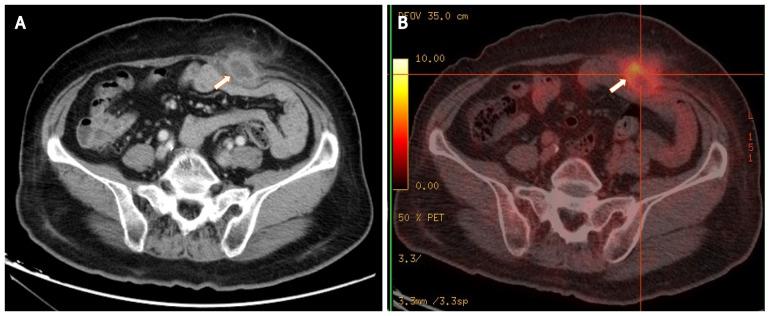

A 72-year-old female patient presented with an enlarged painless mass in the lower abdomen for 1 year. She had a history of obesity, diabetes, and MGUS. Her surgical history was laparoscopic resection for rectal cancer 6 years prior, followed by chemotherapy. She was afebrile. Abdominal examination revealed a smooth abdomen with a clinically palpable solid mass under a laparotomy scar in the left lower quadrant. No obvious tenderness or skin redness was spotted. Laboratory data were not remarkable. Computed tomography scan revealed a low-density mass of 4.8 cm in diameter in the lower abdominal wall, which showed high uptake on positron emission tomography. The preoperative diagnosis was an abscess or tumor, and surgical resection was recommended. The mass was confirmed to be an AA by microbiological and pathological examinations. The patient recovered well after surgery. There was no evidence of recurrence 2 years later.

一名72岁女性患者,下腹部出现无痛性肿块增大1年。她有肥胖、糖尿病和MGUS病史。她的手术史为6年前因直肠癌行腹腔镜切除术,随后进行化疗。她无发热。腹部检查显示腹部光滑,左下腹剖腹手术瘢痕下可触及一个临床可触及的实性肿块。未发现明显压痛或皮肤发红。实验室检查数据无异常。计算机断层扫描显示下腹壁有一个直径4.8 cm的低密度肿块,在正电子发射断层扫描上显示高摄取。术前诊断为脓肿或肿瘤,建议手术切除。经微生物学和病理学检查证实肿块为AA。患者术后恢复良好。2年后无复发迹象。